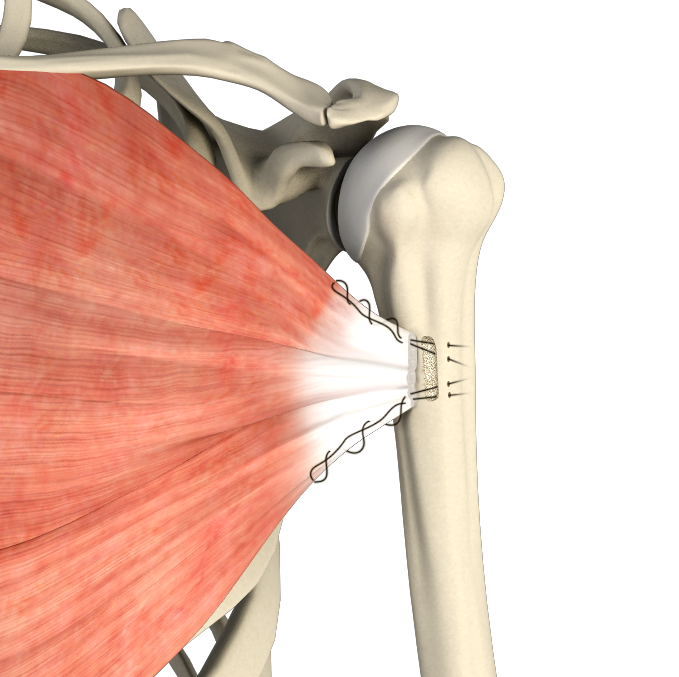

Rotator Cuff Repair

The rotator cuff is a group of 4 muscles in the shoulder joint including the supraspinatus, infraspinatus, teres minor, and subscapularis.

Rotator Cuff Tear

A rotator cuff tear is an injury where one or more of the tendons in the rotator cuff (the group of muscles and tendons that stabilize the shoulder and enable arm movement) become partially or completely torn.